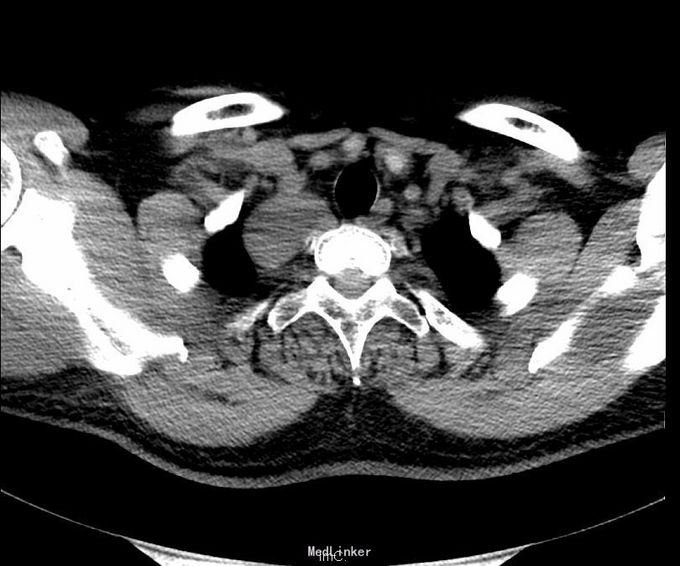

肺功能报告:MMEF轻度下降,V25中度下降,VE>10L。患者存在小气道气流轻度受限,过度通气,肺功能稍受损。 CT胸部增强扫描:右侧胸腔顶部见一大小约4.3*3.4cm软组织密度肿块,边界清楚,边缘光滑,与脊柱呈宽基底相连,增强后肿块明显均匀强化。第三肋骨可见致密结节影。意见:1、右后上纵隔占位,多系肿瘤:神经源性?淋巴源性或其他?2、心包及双侧胸膜稍增厚;3、右侧第3肋腋段致密结节,考虑骨岛可能。

诊断:1、 纵隔肿瘤(右后上,神经源性?淋巴源性?)2、脂肪肝3、脾大4、右第三肋骨骨岛形成5、右上颌窦囊肿 在全麻下右开胸右后上纵隔肿瘤切除术。术中见:1)胸内淡黄色积液50ml,无粘连;2)胸膜无种植;肿瘤对肺叶无侵犯, 肿瘤对心包无侵犯。3)肿瘤位于右后上纵隔约 4*3*3cm大小、包膜完整。4)淋巴结肿大及侵犯情况:无 5)术中冰冻结果:梭形细胞肿瘤,倾向神经源性 。6)术中特殊情况:无 完整切除肿瘤,术中出血不多,未输血,术后患者安返病房,给予对症、支持治疗。